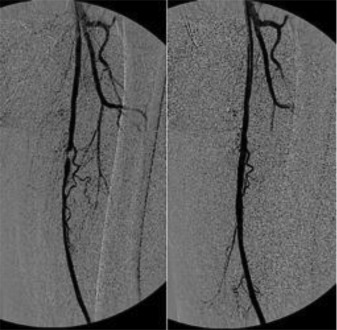

Below: Intraoperative angiography of the superficial femoral artery, before and after stenting.

Source: Figure 1. Intraoperative angiography of the left femoral artery. From “Abnormally high failure rate for femoral angioplasty in patients with pseudoxanthoma elasticum,” by M Ammi, G Kranenburg, L Omarjee, et al. (2015). J Vasc Surg, 1(4), 276-278.